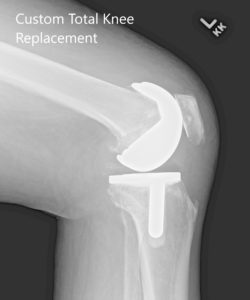

Implants used: Custom femoral implant with 6 mm polyethylene insert with a custom tibial tray with a 38 mm patellar implant.

Postoperative X-ray showing AP and lateral images of the left knee.